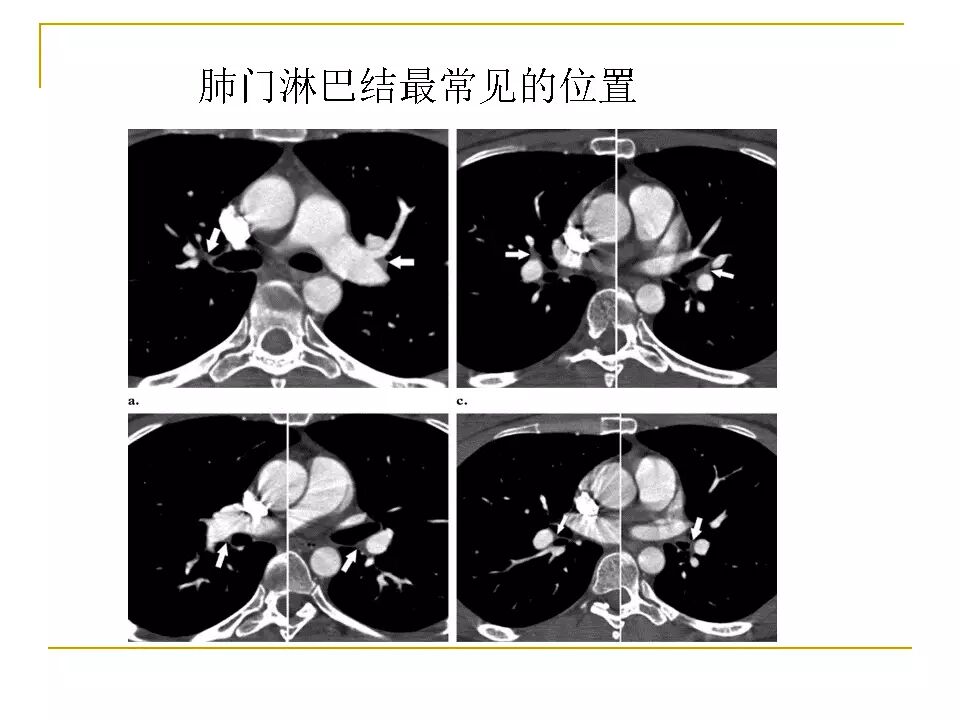

【RadioGraphics】肺动脉栓塞CTA